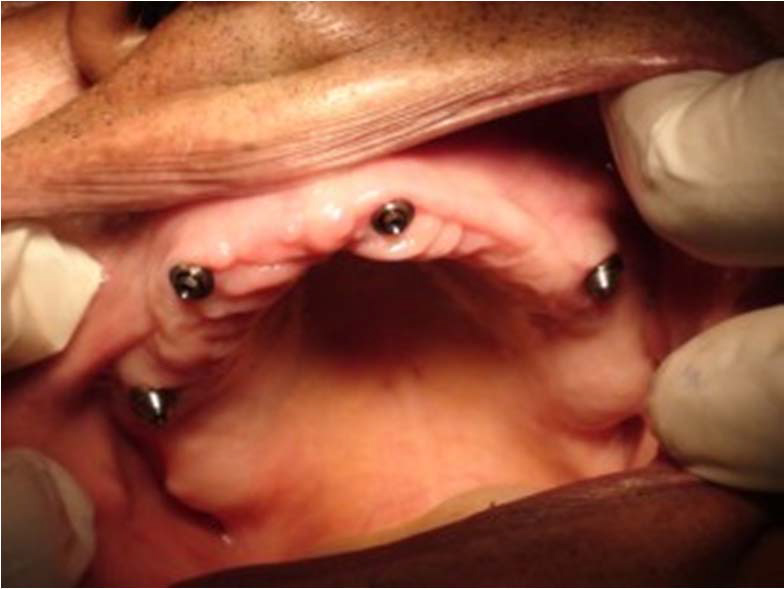

Kulové attachmenty

Sub-Tec Locator®

S pomocí zubních implantátů můžeme díky různým kotevním systémům (třmeny, kulové hlavy, Locatory) zajistit stabilitu a držení protézy nebo při použití většího počtu implantátů zhotovit pevné náhrady – můstky nalepené nebo našroubované na pevno na implantáty.